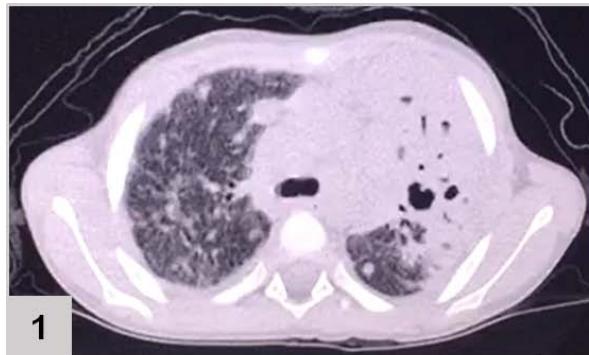

Computerized tomography (CT) of the chest (FIGURE 1)

Figure 1: CT of the chest results: extensive consolidation, with air bronchograms and cystic images in between, in the left lung (3 and 4); ground-glass opacities, diffusion in the lower left lobe (1 and 2); nodular opacity, no sign of calcification in between, on both lungs (1, 2 and 3); reticular and linear opacity and parenchymal bands in the upper lobes (3 and 4); small pleural effusion on the left (1 and 2); adjacent subsegmental atelectasis (2 and 4)

The patient's chest CT scan for the evaluation of pulmonary zygomycosis showed suggestive findings of fungal balls in both lungs, visualized as non-calcified nodular opacities and pleural effusion on the left, which is an infrequent radiological sign[^6], but of great importance for diagnosis, because the mutual presence of multiple fungal balls with pleural effusion are independent predictors of pulmonary zygomycosis[^5].